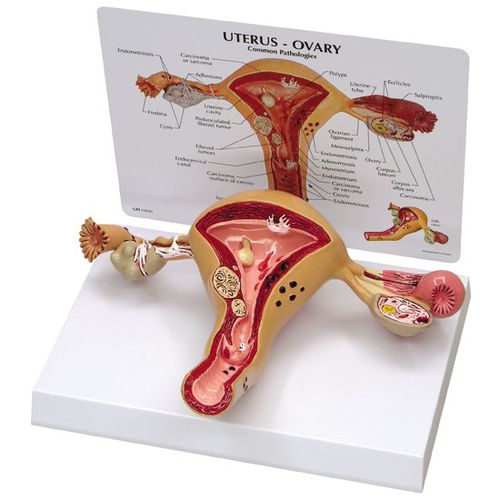

人体模型 骨盤模型 女性 子宮 解剖学的詳細 Amazon | 女性骨盤モデル - 生殖器・血管・神経・筋肉・子宮の詳細なの詳細情報

Amazon | 女性骨盤モデル - 生殖器・血管・神経・筋肉・子宮の詳細な。Amazon.co.jp: 女性 骨盤と 子宮模型 筋肉解剖学 女性骨盤 骨盤底筋と。子宮の解剖模型 - 3480 - GPI Anatomicals - 卵巣の / 実習用 / 女性用。解剖学的詳細を再現した人体模型、頭部と首部が観察可能。- モデル: 人体模型- 部位: 骨盤 大腸 子宮 腹部- 特徴: 解剖学的詳細が再現された構造- 素材: プラスチック製- サイズ: 約30cmの高さご覧いただきありがとうございます。絵画用に模型を購入しましたが使用をしないままでしたのでお譲りします⭐︎とても丁寧な作りでおすすめです◎。h20-1-1280x720.jpg。